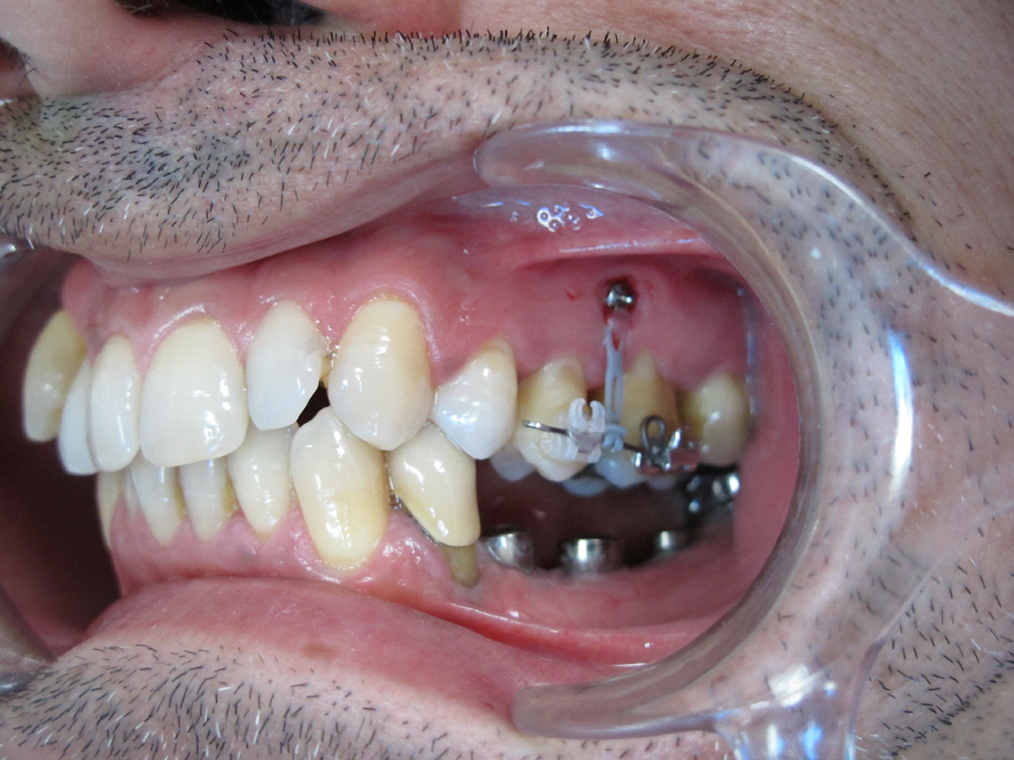

Présentation cas clinique

L’orthodontie linguale invisible

L’orthodontie linguale est une technique qui permet la correction de toutes les malocclusions, en toute discrétion.

Les attaches orthodontiques sont collées sur la face interne des dents : on ne voit donc pas l’appareillage.

En revanche, la phase d’adaptation à l’appareil est plus longue et varie en fonction des patients. Il peut y avoir au début une légère perturbation de l’élocution et une gêne de la langue.